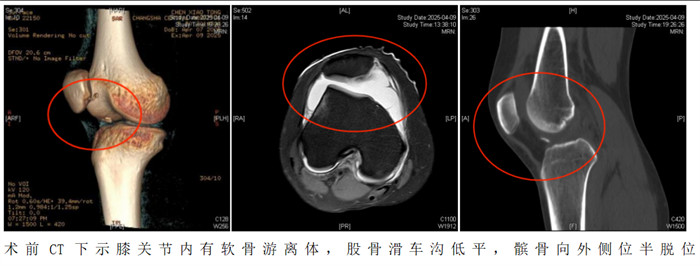

“患者入院后,我们为她制定了周密的个性化治疗方案,采用‘关节镜下髌骨成形术+纽扣十字缝合法软骨修复术’帮助恢复膝关节功能。”据维多利亚老品牌76696vic(南华大学附属长沙中心医院)运动医学、创伤关节、骨病科主任丑克介绍,这项联合术式在省内少见,因患者游离软骨骨碎片大,软骨下骨骨质有血运,髌骨内下缘软骨缺损面积大,通过高强度缝线采用纽扣十字缝合法原位缝合剥脱的软骨块成形髌骨,犹如为膝关节打造了一个防护网。手术过程顺利,术后患者恢复良好。

2.如果出现以下情况需要考虑手术治疗。初次脱位后出现髌骨或股骨软骨骨折导致关节内出现游离体时,必须手术治疗。关节镜是目前成熟的关节内镜技术,医生通过内镜,直视下观察髌骨的损伤,取出游离体并修复软骨,行内侧支持带紧缩和外侧支持带松解术,即可取得满意的疗效。该手术是微创手术操作,创伤小,恢复快,多数患者术后第1天即可下地活动。